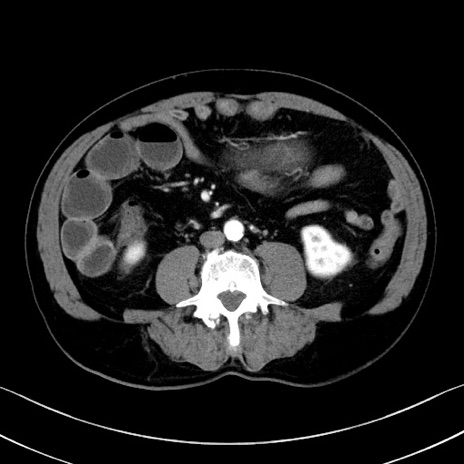

症例35(横断像)

【症例】70歳代 男性

【主訴】腹部膨満、嘔吐

【現病歴】昨日より腹部膨満感出現。本日増悪し、仙痛出現。嘔吐あり、受診。

【既往歴】糖尿病、胆摘後

【身体所見】BP 149/80mmHg、HR 74/min、BT 35.9℃、腹部:膨満、軟、圧痛なし。腸雑音減弱あり。上腹部正中切開瘢痕あり。

【データ】WBC 13500、CRP 1.72